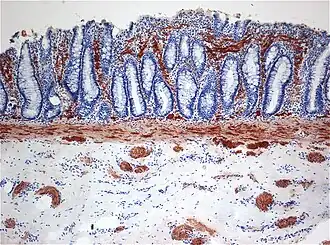

| Histopatologia da Doença de Hirschsprung mostrando fibras nervosas positivas (marrons) de acetilcolina esterase (AchE) anormais na mucosa | |